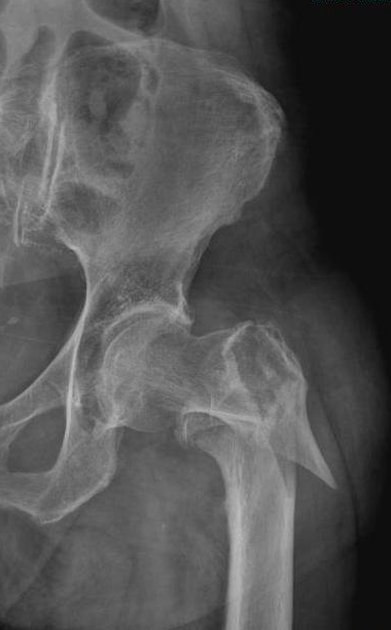

Fractures around the greater and small trochanter of the femur are more convenient in terms of blood flow and union. However, these fractures are unstable and susceptible to separation due to the pulling force of strong muscles adhering to fractures.

In the past, fractures in these regions, were treated with prosthesis applications instead of union, due to old age and osteoporotic bone structures of the patients. However, because of the strong muscle groups in this region affects the mechanical ability of prostheses negatively, this method do not provide an adequate satisfaction.

Due to the fact that modern, powerful, easily applicable fixing devices can be placed with minimal incisions to the patients, the prosthesis is not generally applied in the treatment of trochanteric fractures. A convenient pre-surgery planning and the proper application of fixation devices (nails) allow patients to walk in the early stages and protected from the handicaps of prosthetic surgery.